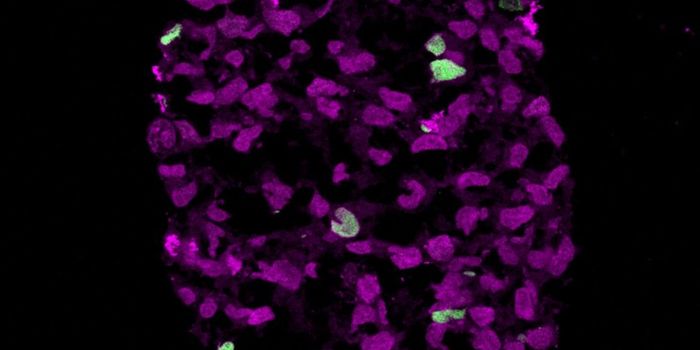

FEB 21, 2023Cell & Molecular BiologyThe Griffith Lab at UNC discovered telomeric protein & potential biomarker VR (green), shown in the nuclei (blue) of hum ...